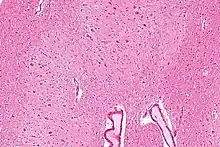

The dentate nucleus is a cluster of neurons, or nerve cells, in the central nervous system that has a dentate – tooth-like or serrated – edge. It is located within the deep white matter of each cerebellar hemisphere, and it is the largest single structure linking the cerebellum to the rest of the brain.[1] It is the largest and most lateral, or farthest from the midline, of the four pairs of deep cerebellar nuclei, the others being the globose and emboliform nuclei, which together are referred to as the interposed nucleus, and the fastigial nucleus. The dentate nucleus is responsible for the planning, initiation and control of voluntary movements. The dorsal region of the dentate nucleus contains output channels involved in motor function, which is the movement of skeletal muscle, while the ventral region contains output channels involved in nonmotor function, such as conscious thought and visuospatial function.

The dentate nucleus is highly convoluted, with gyri (ridges on the cerebral cortex) and sulci (furrows or grooves on the cerebral cortex). Its formation is coincident with a critical period of extensive growth in the fetal dentate. The dentate nucleus becomes visible in the cerebellar white matter as early as 11–12 weeks of gestation, containing only smooth lateral (towards the side(s) or away from the midline) and medial (towards the midline) surfaces. During this time, the neurons of the dentate nucleus are similar in shape and form, being mainly bipolar cells.[2]

The architecture of cerebellum has a form that resembles the structure of a crystal, so a slice anywhere in the cerebellum gives repeated architecture. The eight cerebellar nuclei, located within the deep white matter of each cerebellar hemisphere, are grouped into pairs, with one of each pair in each of the two hemispheres. As a chunk of tissue, the dentate nucleus with overlying cerebellar cortex makes up a functional unit called the cerebrocerebellum. Thus, there is a part of cerebellum that communicates exclusively with the dentate nucleus.[4]

Morphology